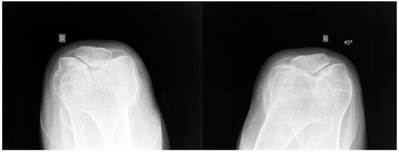

Group 2: Patients showed excessive femoral anteversion of the hips secondary to significant acetabulo-femoral dysplasia (IR-internal rotation: 90 degrees, ER-external rotation: 30 degrees). We measured the torsion of the femur by means of CT scan. There was femoral anteversion of right hip of 38° and of the left hip of 45 ° respectively in a 13-year-old-boy (fig 4). CT scan to measure the rotation of the knees showed internal rotation 7° of the right knee and 20° rotation of the left knee in connection with trochlear dysplasia (fig 5).

Fig 4

Axial hip CT scan showed femoral anteversion of the hips secondary to significant acetabulo-femoral dysplasia (IR-internal rotation: 90 degrees, ER-external rotation: 30 degrees). We measured the torsion of the femur by means of CT scan. There was femoral anteversion of right hip of 38° and of the left hip of 45 ° respectively in a 13-year-old-boy.